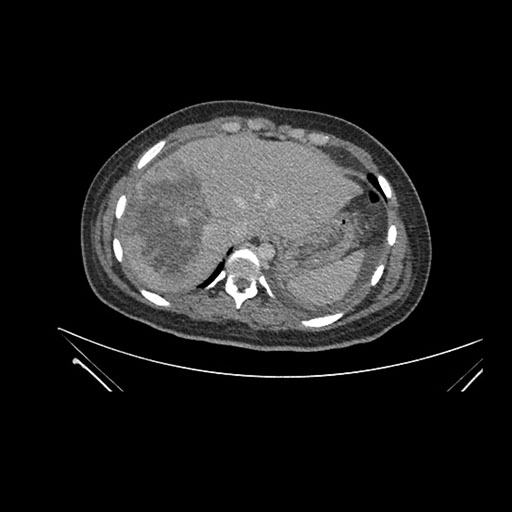

Axial Arterial